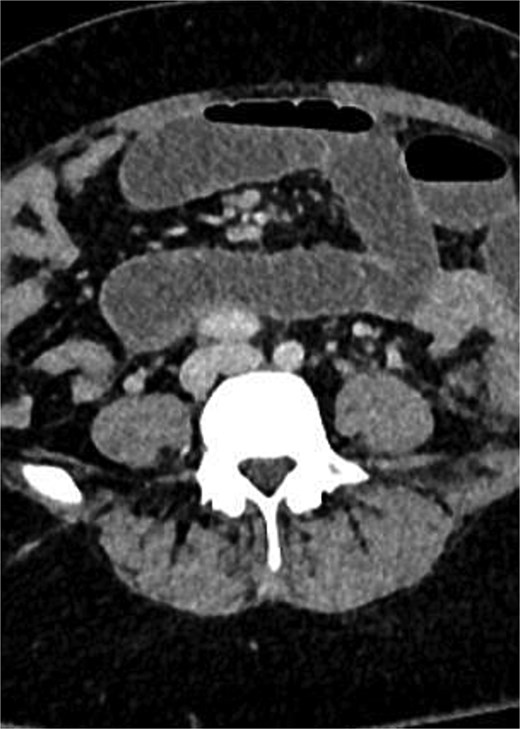

A computed tomography (CT) scan of the abdomen and pelvis showed complex and aggressive disease involving the pelvic area, affecting the urinary bladder, cervix, sigmoid colon, and the left adnexa. Additionally, a loop of small bowel was involved in the inflammatory process, leading to a closed-loop small bowel obstruction. Differential diagnoses included infiltrative malignancy, tuberculosis, or actinomycosis. A CT scan of the thorax was performed to rule out any pathology or metastasis to the lungs.

CT images with Fig. 1: Pelvic mass involving sigmoid colon, uterus, urinary bladder, left fallopian tube and ovary. Figure 2: Small bowel obstruction secondary to the mass.